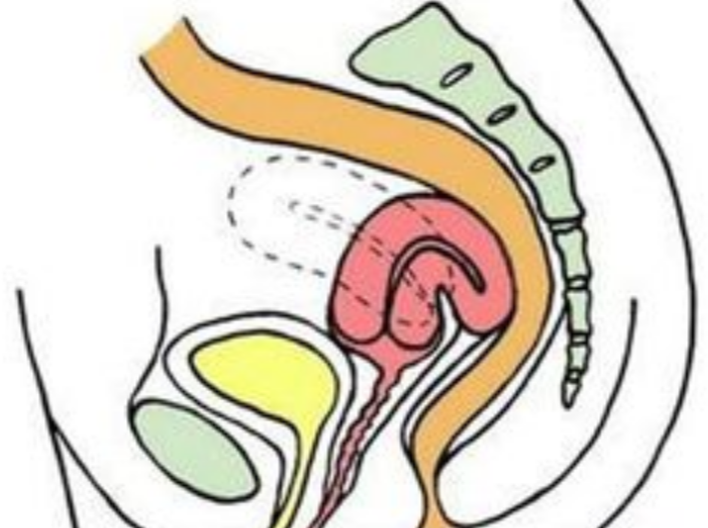

治療中人工陰道漫畫

治療中人工陰道

治療中人工陰道漫畫